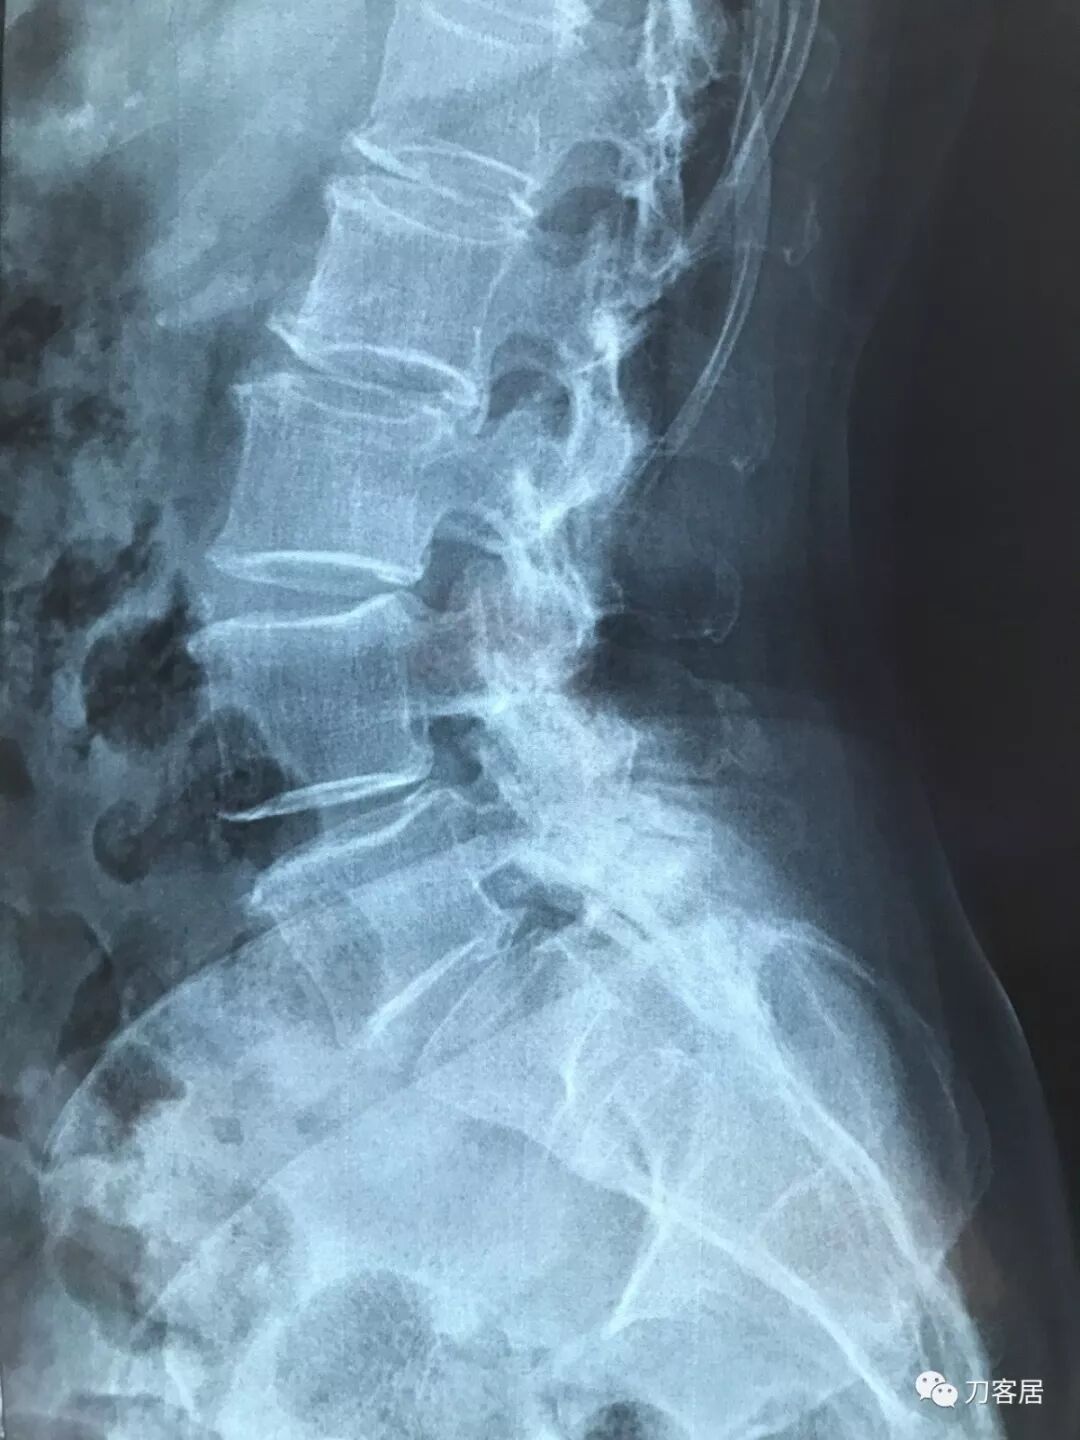

比如以下这几张翻拍图

倾斜、反光、透亮

对于医生阅片造成很大的阻碍

图2:透光

图3:反光